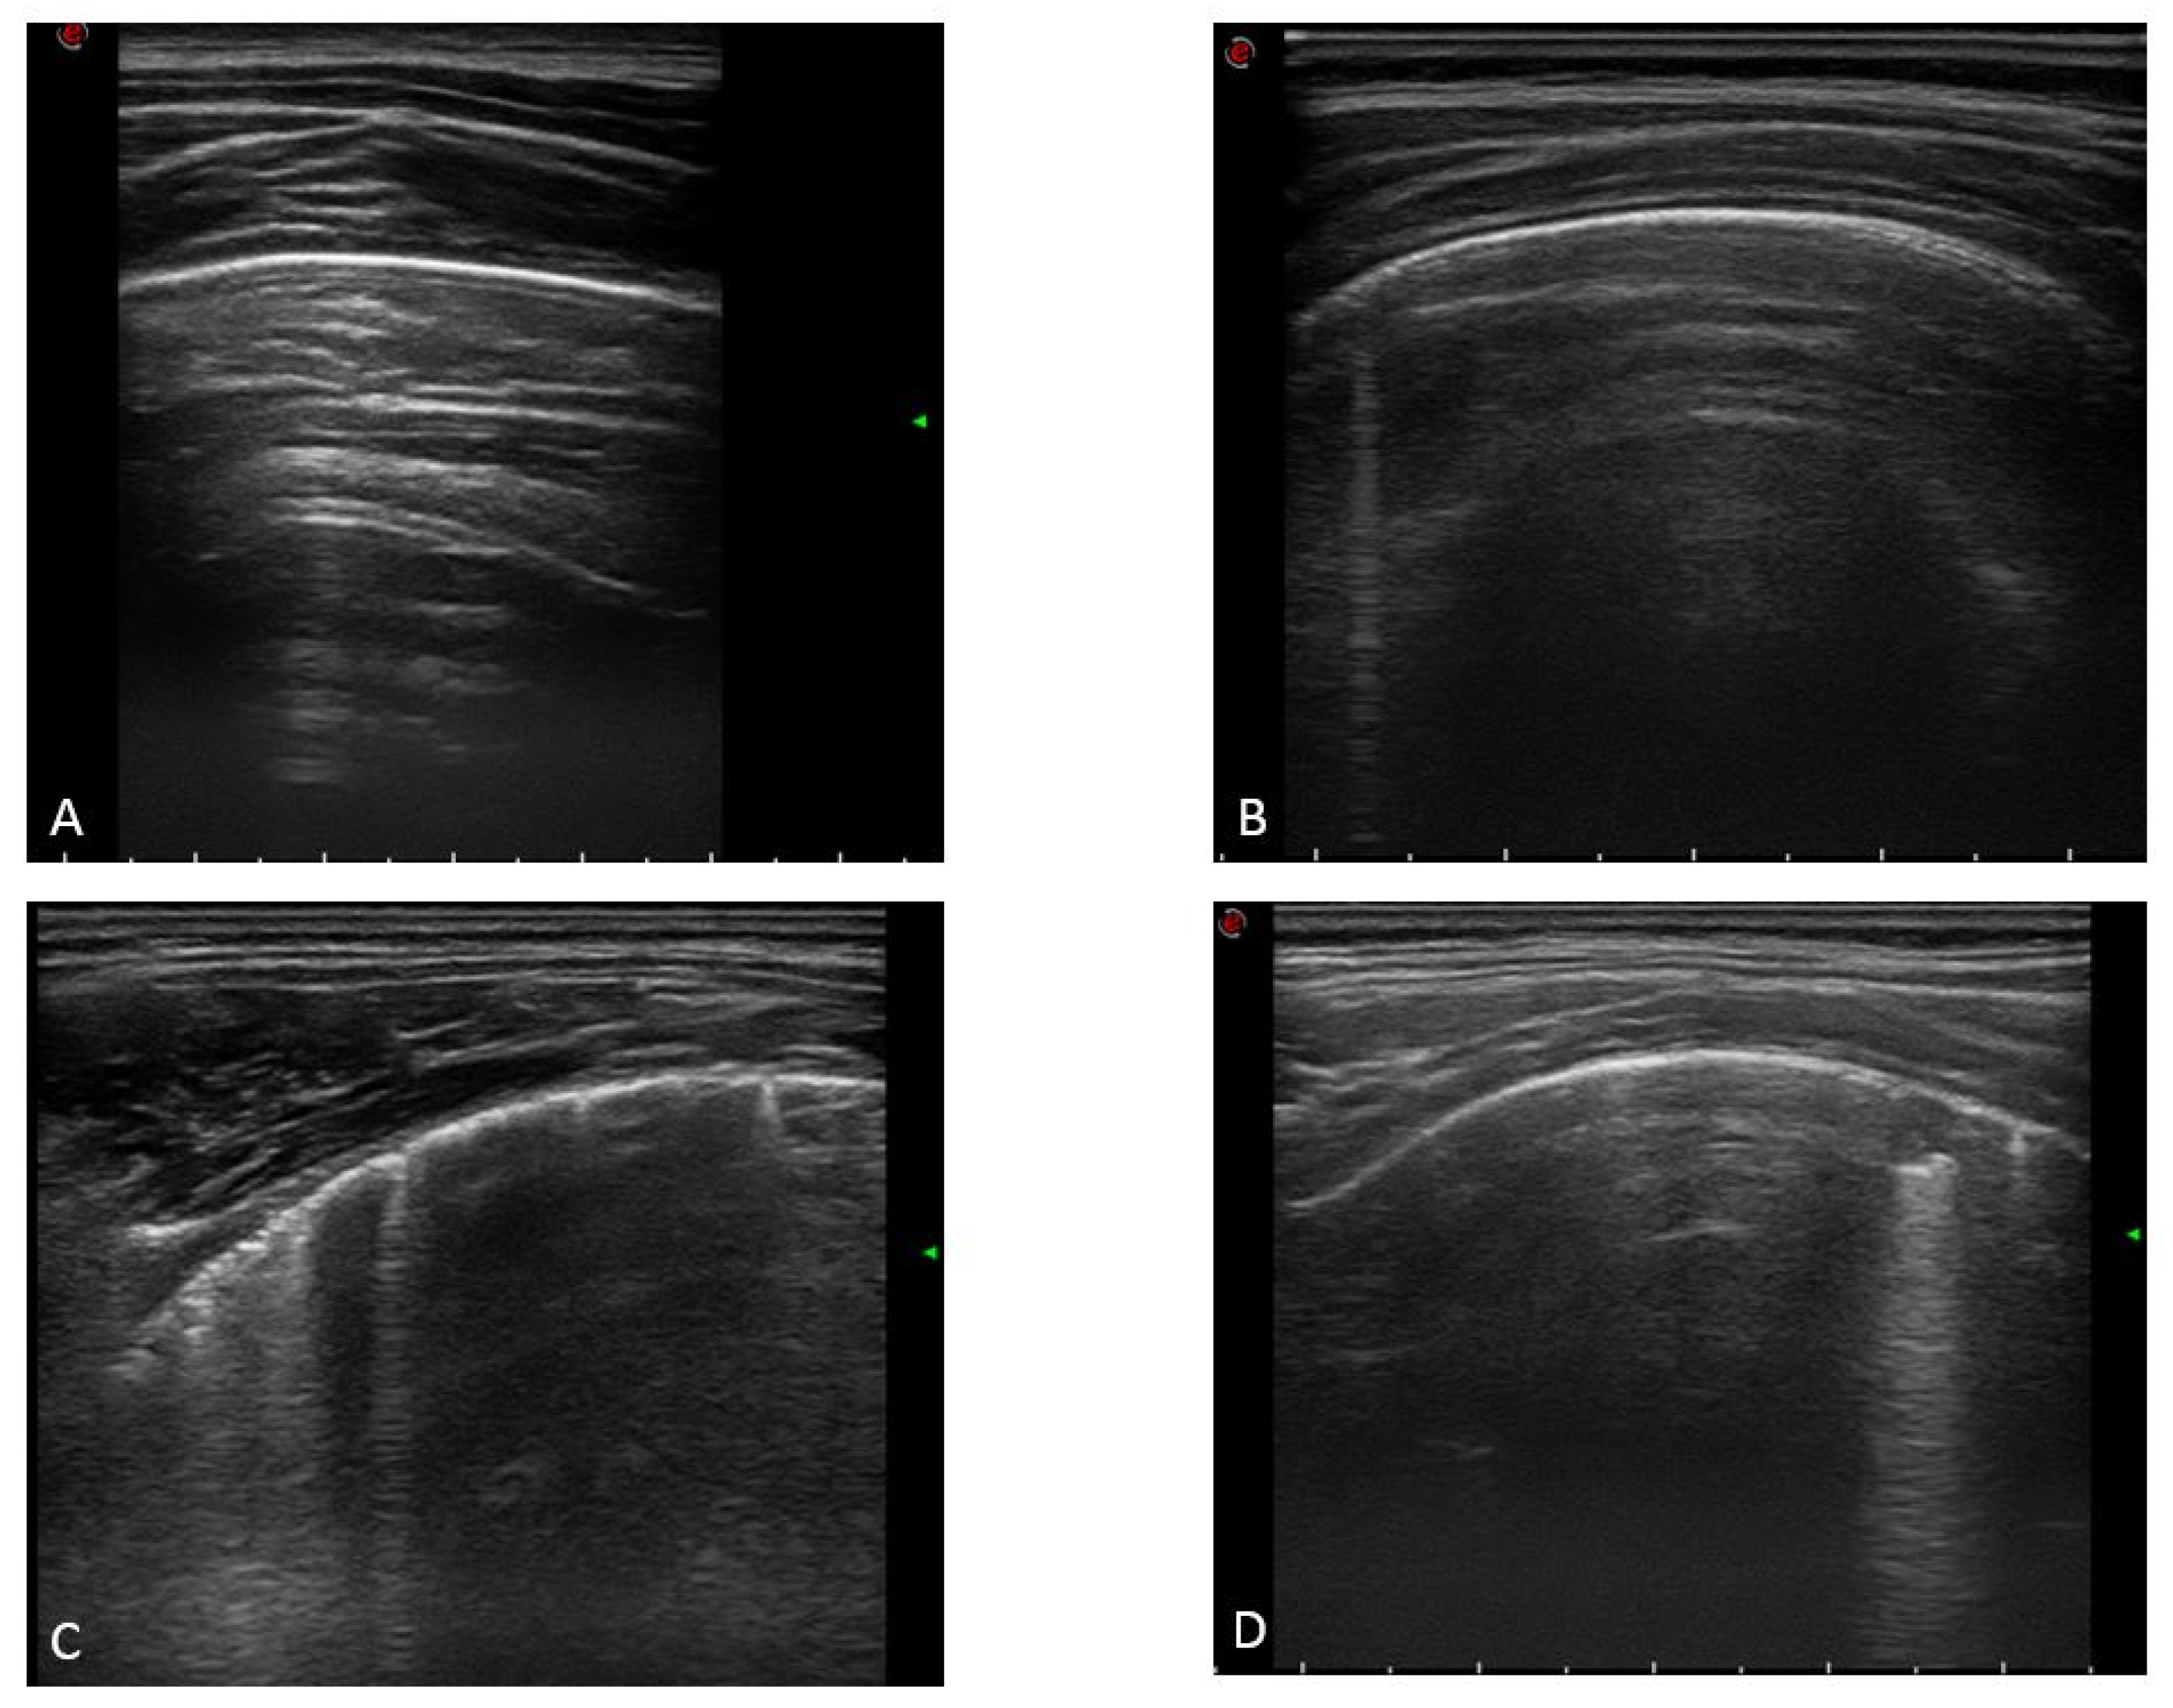

3.2. LUS Findings